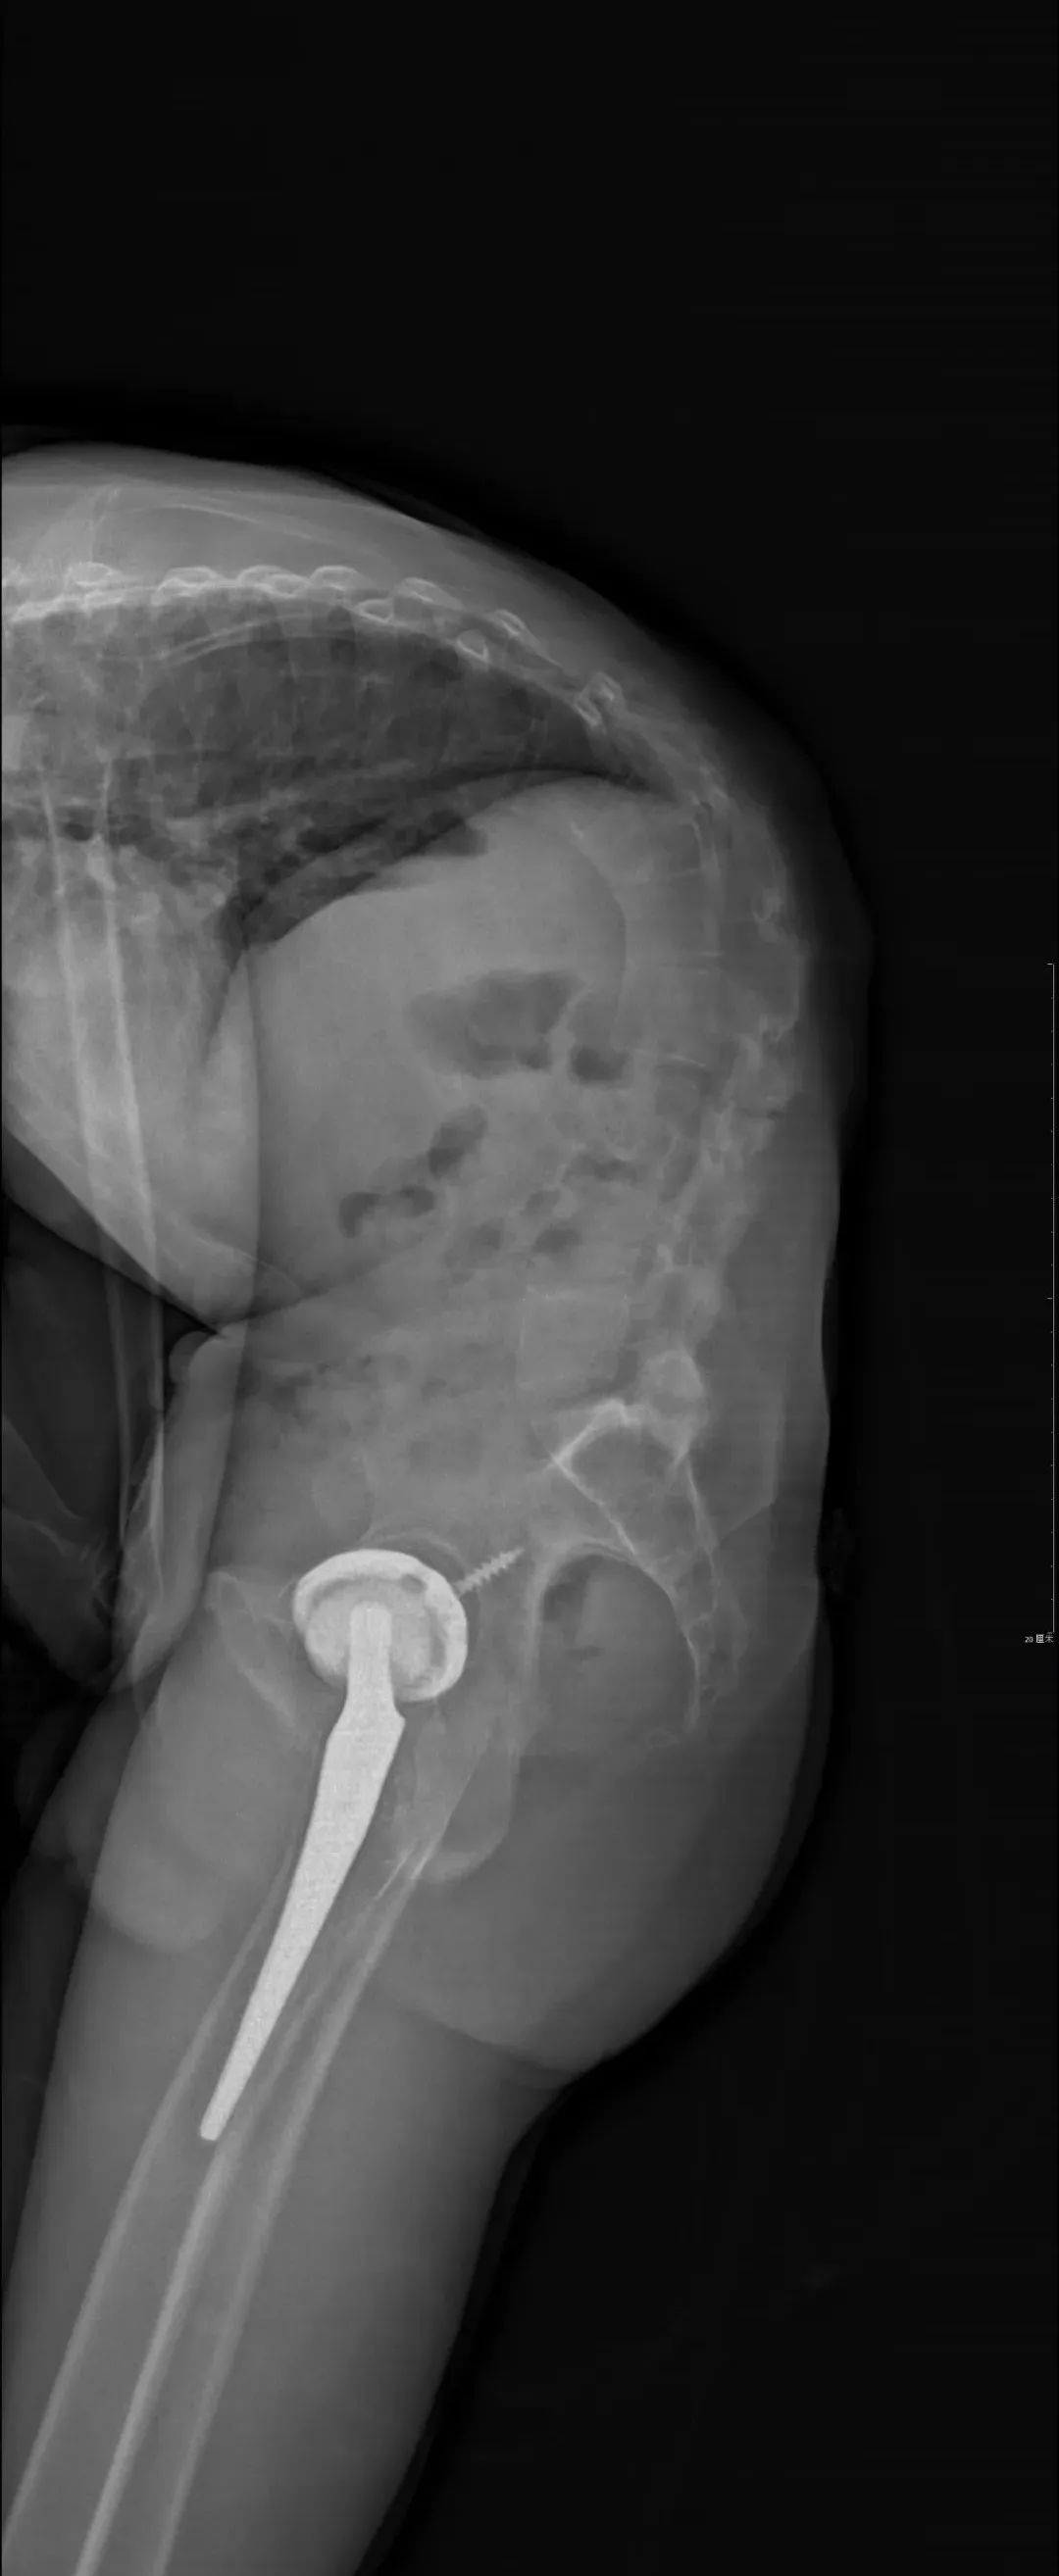

患者张先生(化名),10余年前确诊为强直性脊柱炎,间断口服药物治疗。10年前因此疾病在我院进行了全髋关节置换术,术后髋关节活动良好,那时脊柱没有出现畸形,还是可以直立的正常人。后来随着疾病的进展,脊柱后凸逐渐加重,于我院就诊时患者的胸腰椎后凸畸形已近90度,站立时的体态就如同鞠躬,睡觉无法平躺,严重影响生活质量。

患者又回到了最信任的北京积水潭医院,找到了髋关节手术的主刀医生周一新主任,由周主任介绍到脊柱外科。脊柱外科经过全科查房讨论,制定周密的术前规划,综合考虑患者的直立、平视、端坐、平躺等功能,设计截骨位置并计算截骨角度,最终确定了L3、T12双节段经椎弓根截骨的矫形方案。在麻醉科、手术室、肌电图室、ICU、输血科、脊柱外科等多方面合作下,手术顺利完成。患者术后即可完全平躺,下地后可完全直立并且平视。手术效果非常满意,患者重新挺起胸膛,开启新的人生。